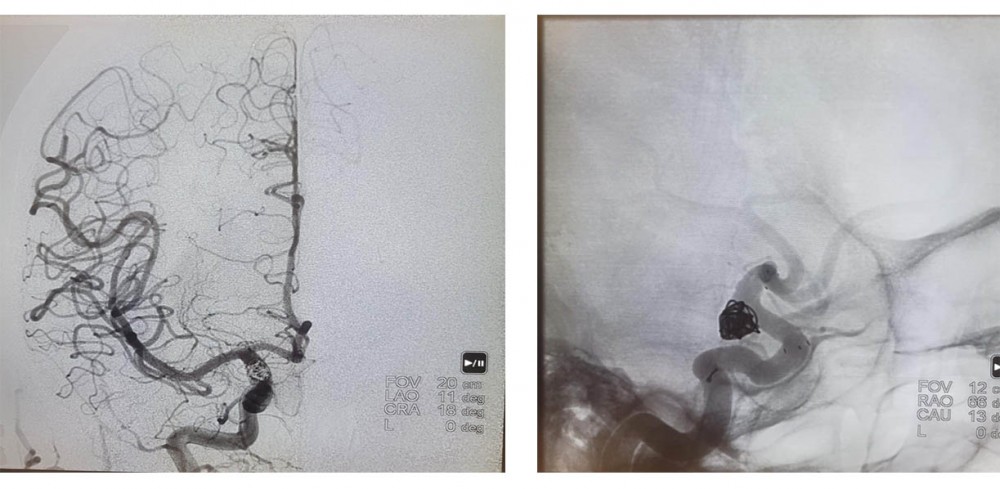

Консилиумом специалистов учреждения (нейрохирургов, акушеров-гинекологов, лучевых диагностов) было принято решение о дообследовании беременной. Результаты КТ-ангиографии выявили, что внутричерепное кровоизлияние обусловлено разрывом внутричерепной аневризмы коммуникантного сегмента правой внутренней сонной артерии. Иными словами, выпячивание стенки кровеносного сосуда просто прорвалось. Ситуация была критическая.

Характер аневризмы не оставлял докторам выбора — требовалась реконструкция пораженной артерии с помощью стента. Единственным адекватным методом лечения являлась внутрисосудистая окклюзия аневризмы (намеренная закупорка) спиралями со стент-ассистенцией. При этой процедуре необходимо вводить препараты, разжижающие кровь. Однако выполнение одномоментного родоразрешения и такой операции на фоне снижения свертывания крови представляло повышенную опасность ввиду высокого риска маточного кровотечения. Комплекс сложнейших задач встал перед мультидисциплинарной бригадой врачей центра.

Днем 31 декабря, в преддверии Нового года, бригада нейрохирургов в составе ведущего сосудистого нейрохирурга, заведующего нейрохирургическим отделением № 3 к.м.н. Андрея Евгеньевича Петрова и врача-нейрохирурга к.м.н. Аркадия Александровича Иванова в Перинатальном центре выполнила оперативное лечение разорвавшейся аневризмы.

ДО эмболизации

после

ПОСЛЕ  эмболизации

Через прокол на руке ввели специальные микроспирали, которые закрыли разрыв аневризмы, и поставили стент, который не позволит ситуации повториться (имплантировали ассистирующий стент на фоне двойной дезагрегантной терапии).